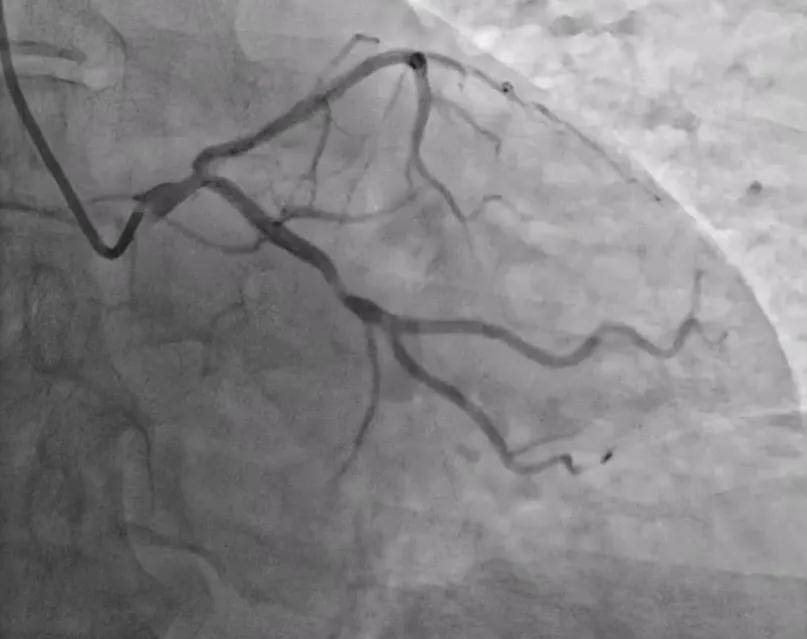

在机器人辅助下,团队顺利将LAD及LCX导丝推送至血管远端。随后机器人沿LCX导丝推送球囊预扩张,使用刻痕球囊再次处理后,成功植入支架一枚,多体位造影显示支架贴壁良好,膨胀良好,无支架边缘夹层等并发症。整个手术历时约40分钟,结果圆满。

图说 / 造影提示LCX支架植入效果良好